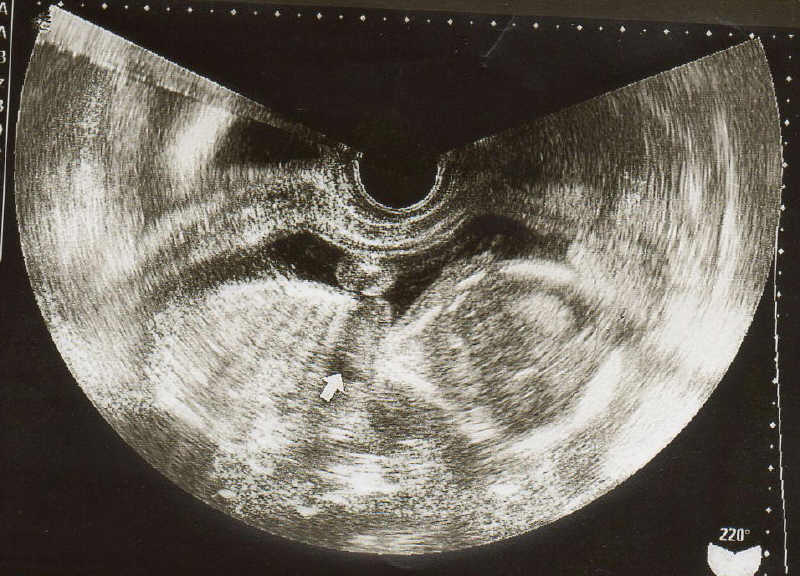

5 産科一般超音波検査 初期編 正常所見4 7週 日本産婦人科医会